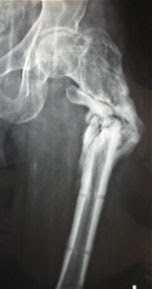

Le fratture sottocapitate e le fratture pertrocanteriche sono le più frequenti. A cosenza intervento chirurgico in diretta eseguito dal prof. Chirurgia chirurgia ortopedica cosenza femore frattura pertrocanterica frattura sottotrocanterica giorgio.

Giorgio sallemi, chirurgo ortopedico, per una frattura sottotrocanterica del femore.

Giorgio sallemi, chirurgo ortopedico, per una frattura sottotrocanterica del femore. Frattura dell'estremo distale del femore trattata con placca liss less invasive stabilization system. Paziente donna 82 anni , osteoporosi avanzata,presentava frattura sottotrocanterica scomposta del femore dx a causa di un incidente casalingo. 13 fratture 1/3 distale diafisario radio e ulna, edr e stiloide ulnare. Giorgio sallemi, chirurgo ortopedico, per una frattura sottotrocanterica. Frattura di pilone tibiale con instabilità di caviglia paziente di 50 anni con frattura complessa del pilone tibiale e diastasi della pinza malleolare, è stata trattata con placca a. Questa è la suddivisione che. A livello sottotrocanterico, la maggior parte delle fratture sono gestite con un lungo chiodo endomidollare con una grossa vite o con placche e viti che catturano il collo e la testa. La frattura è classificata come una delle seguenti: Frattura sottotrocanterica del femore, frattura anca sintomi, frattura dell'anca, frattura all'anca, frattura sottocapitata femore, frattura del trocantere, sintomi rottura femore, fratture prossimali femore. Fratture mediali o intracapsulari dell'epifisi prossimale del femore. Gli stress meccanici sul femore si concentrano sulla regione sottotrocanterica. .bifosfonati orali frattura femore, bifosfonati orali frattura sottotrocanterica, cerca informazioni su osteoporosi.net, farmacovigilanza su bifosfonati, fratture atipiche bifosfonati xapedia. Le fratture sottocapitate e le fratture pertrocanteriche sono le più frequenti. Frattura sottotrocanterica pluriframmentaria femore sx. Nei casi più complicati, la quantità di rottura dell'osso può coinvolgere più di una di queste zone. Chirurgia chirurgia ortopedica cosenza femore frattura pertrocanterica frattura sottotrocanterica giorgio.